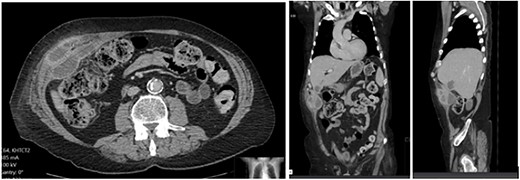

A 65-year-old gentleman with a body mass index of 29.6 and medical history of Guillain–Barré syndrome, type 2 diabetes mellitus, hypertension, and chronic pain was referred to our outpatient clinic with intermittent upper abdominal pain. His surgical history included an open appendicectomy. He was wheelchair-bound outside his home and received weekly assistance from a carer. On examination he was anicteric. His abdomen was soft, but a mildly tender mass was palpable in the right upper quadrant. An initial computed tomography (CT) scan showed thickening of the gallbladder and a collection extending from the fundus and infiltrating the anterior abdominal wall (Fig. 1). Further scans showed extension of the collection towards the midline (Fig. 2). He subsequently presented to the emergency department with purulent discharge from an external orifice adjacent to the umbilicus. An ultrasound-guided 6Fr pigtail drain was then placed into the known abdominal wall collection.

CT abdomen with portal venous contrast showing gallbladder collection extending to lateral abdominal wall.

CT abdomen with portal venous contrast in axial plane showing extension of collection towards the paraumbilical region.